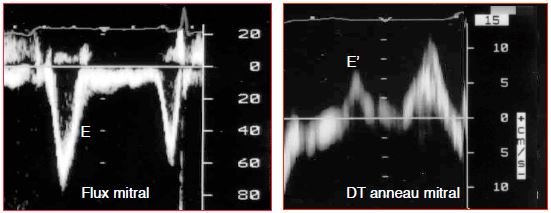

- Indices dérivés des flux de remplissage à l'examen Doppler (flux dans les veines pulmonaires et à travers la valve mitrale). Comme ils dépendent du gradient de pression, ces flux sont tributaires de la compliance des chambres cardiaques et de la pression intrathoracique; de ce fait, ils ne sont pas plus pertinents que les pressions de remplissage. De plus, ils sont indissociables de la fonction diastolique et n'ont pas de valeur pour évaluer la volémie en cas de dysfonction diastolique. Leur corrélation à la POG n'étant fiable que lorsque cette dernière est élevée, ils n’ont aucune portée pratique pour la mesure de l’hypovolémie (Figure 6.42).

Figure 6.42 : Effet de la volémie sur les flux veineux pulmonaire (FVP) et mitral, lorsque ceux-ci sont normaux. Comme la POG est basse en hypovolémie, la composante systolique du FVP est élevée, puisque la POG est sa pression d’aval (la valve mitrale est fermée). Par contre, le flux mitral E est faible car la POG est sa pression d’amont (pression motrice). La tachycardie fait fusionner les flux E et A en une seule onde méso-télédiastolique. En hypervolémie, la POG est haute ; la composante systolique du FVP est freinée ; la majeure partie du flux passe en diastole, lorsque la mitrale est ouverte et que le VG se relâche. L’élévation de la POG augmente la vélocité du flux E. Toutefois, la dysfonction diatolique reproduit les mêmes modifications de flux. En tant que telle, l’image des flux ne permet pas de dissocier les effets de la volémie de ceux de la fonction diastolique des ventricules. La différenciation du flux mitral représentée ici n'est réaliste que si la valve mitrale, la fonction systolique et la fonction diastolique du VG sont parfaitement normales et ne varient pas au cours des modifications du volume circulant.